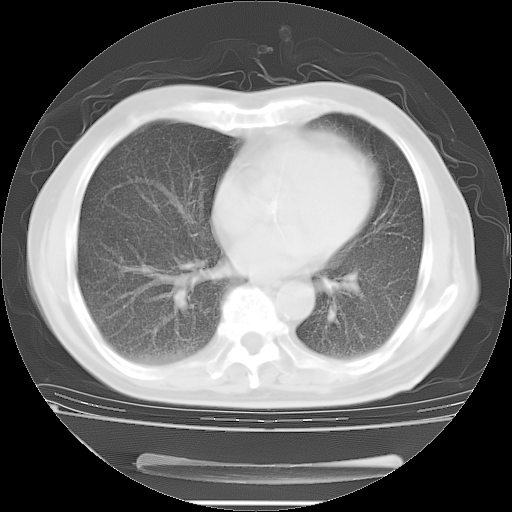

今天复查肺部CT,发现双肺广泛磨玻璃样改变。所以我把3月19日和5月9日相隔50天的肺部CT上传。请大家会诊。

2009年3月19日肺部CT片。

5月9日肺部CT(在4月27日齐鲁医院肺部CT描述部分肺组织磨玻璃样改变,12天后肺组织广泛磨玻璃样改变)